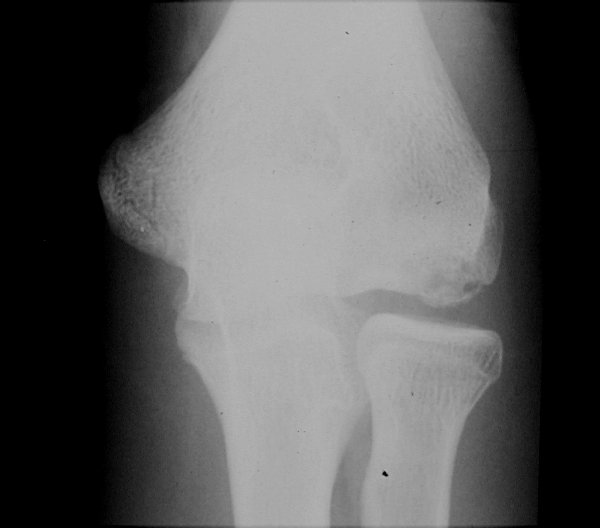

Return to Medial Epicondyle Fracture (Humerus)